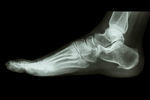

足底筋膜炎/足裏の痛み

【症例】足底筋膜炎

足底筋膜炎の施術をご希望の方へ